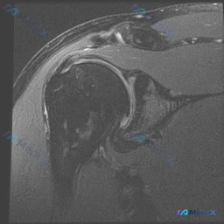

整理了一份肩部MRI病例讨论材料,医生的核心问题是排查盂唇病变,但看影像发现了一些矛盾点。先放MRI T2序列冠状位的分析: 1. 骨性结构:肱骨头、肩峰及锁骨远端轮廓尚可,未见骨折线或骨髓水肿 2. 肌腱与肩袖:冈上肌腱在肱骨大结节止点处形态异常,连续性中断,T2高信号 3. 关节与滑囊:肩峰下-...

最近整理了一份肩部MRI的病例讨论材料,患者主要问题是肩部疼痛,但问题明确指向"盂唇病变"范畴。先看T2冠状位图像的关键发现: 1. 冈上肌腱在肱骨大结节止点处有显著高信号,连续性可能中断 2. 肩峰下-三角肌下滑囊有明显的高信号积液 3. 关节盂唇区域信号存在改变 大家觉得这个病例更符合哪种诊断?...

看到一个肩部MRI(冠状位)的病例资料,用户最初的问题是关于「盂唇病理」,但整理的分析报告里有几个点挺值得讨论的: 先放影像的关键发现: - 冈上肌腱连续性中断,断端回缩,伴冈上肌肌腹萎缩、脂肪浸润 - 肩峰下-三角肌下滑囊积液,肩峰下间隙变窄,肱骨头上移 - 肱骨头大结节下方骨髓水肿 - 盂唇形态...

看到一个肩关节MRI病例资料,有个比较有意思的点:用户的问题是「What is the noticeable abnormality in this image?Labral pathology」(图像中明显的异常是什么?盂唇病变),但整理的影像分析报告核心发现是冈上肌腱全层撕裂。 先把报告里的关键...

看到一个肩关节MRI影像分析的病例材料,影像为冠状位T2加权图像,主要发现如下: 1. 冈上肌腱远端附着处全层撕裂,T2序列显示高信号液体填充 2. 肩峰下-三角肌下滑囊内有明显积液 3. 盂肱关节腔内有显著液体潴留 用户的核心问题是关于「盂唇病变」的可能性。这个病例有几个点值得讨论: - 冈上肌腱...